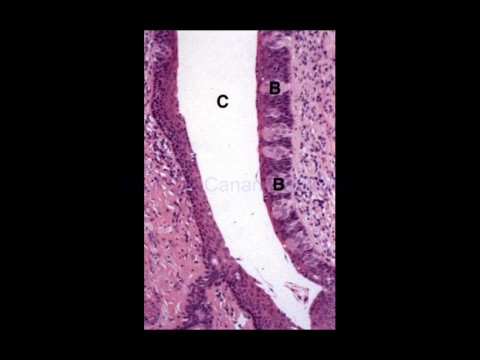

Page 50 - Sindirim Kanalı ve üst sindirim

20-Apr-20                                         Üst Sindirim Sistemi,                                                    50